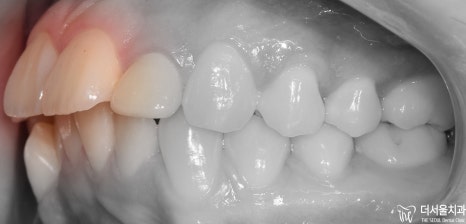

진짜 옆에서 봤을 때 입술이 많이 튀어나와

있는 것을 볼 수 있습니다.

측면 사진을 보게 되면 앞니들이 앞쪽으로

뻐드러져 있는 모습을 볼 수 있으며 이에 따라

당연히 연조직 또한 돌출된 느낌을 받게

될 수밖에 없습니다.

게다가, 구치부를 봤을 때는 삐뚤빼뚤한

총생의 형태도 같이 관찰이 되는데

이는 전체 인비절라인 교정 치료를 하면서

같이 치료를 해드릴 예정입니다.